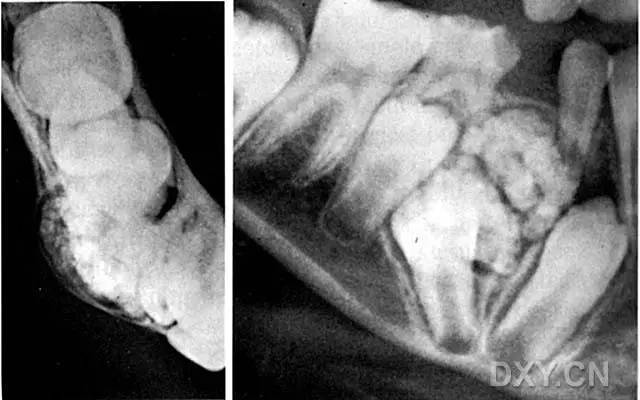

口腔影像案例大全 !牙医看懂影像才能游刃

640x400 - 32KB - JPEG

口腔常见典型病变的X线影像

800x644 - 41KB - JPEG